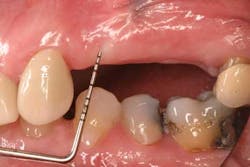

Mucograft® is an example of a xenograft material that has been used in lieu of autogenous grafts to increase keratinized tissue around dental implants (21). Made of porcine collagen, this material has a compact outer layer that can be left exposed to the oral environment and a spongy inner layer that facilitates a blood clot and promotes angiogenesis. A major advantage in using this material for increasing keratinized tissue around dental implants is that it can be used in challenging areas with little to no attached soft tissue because primary closure over this graft material is not needed and it can be left exposed (Figs. 3a-3c).

Fig. 3a: Edentulous Nos. 12 and 13 slated for implant therapy with a limited amount of keratinized tissue.

Fig. 3b: Soft tissue Mucograft placed at the time of implant surgery in order to augment keratinized tissue height and thickness. Primary closure was not obtained over this graft.

Fig. 3c: Final restorations showing a large increase in the height of keratinized tissue, facilitating oral hygiene and increasing plaque resistance.